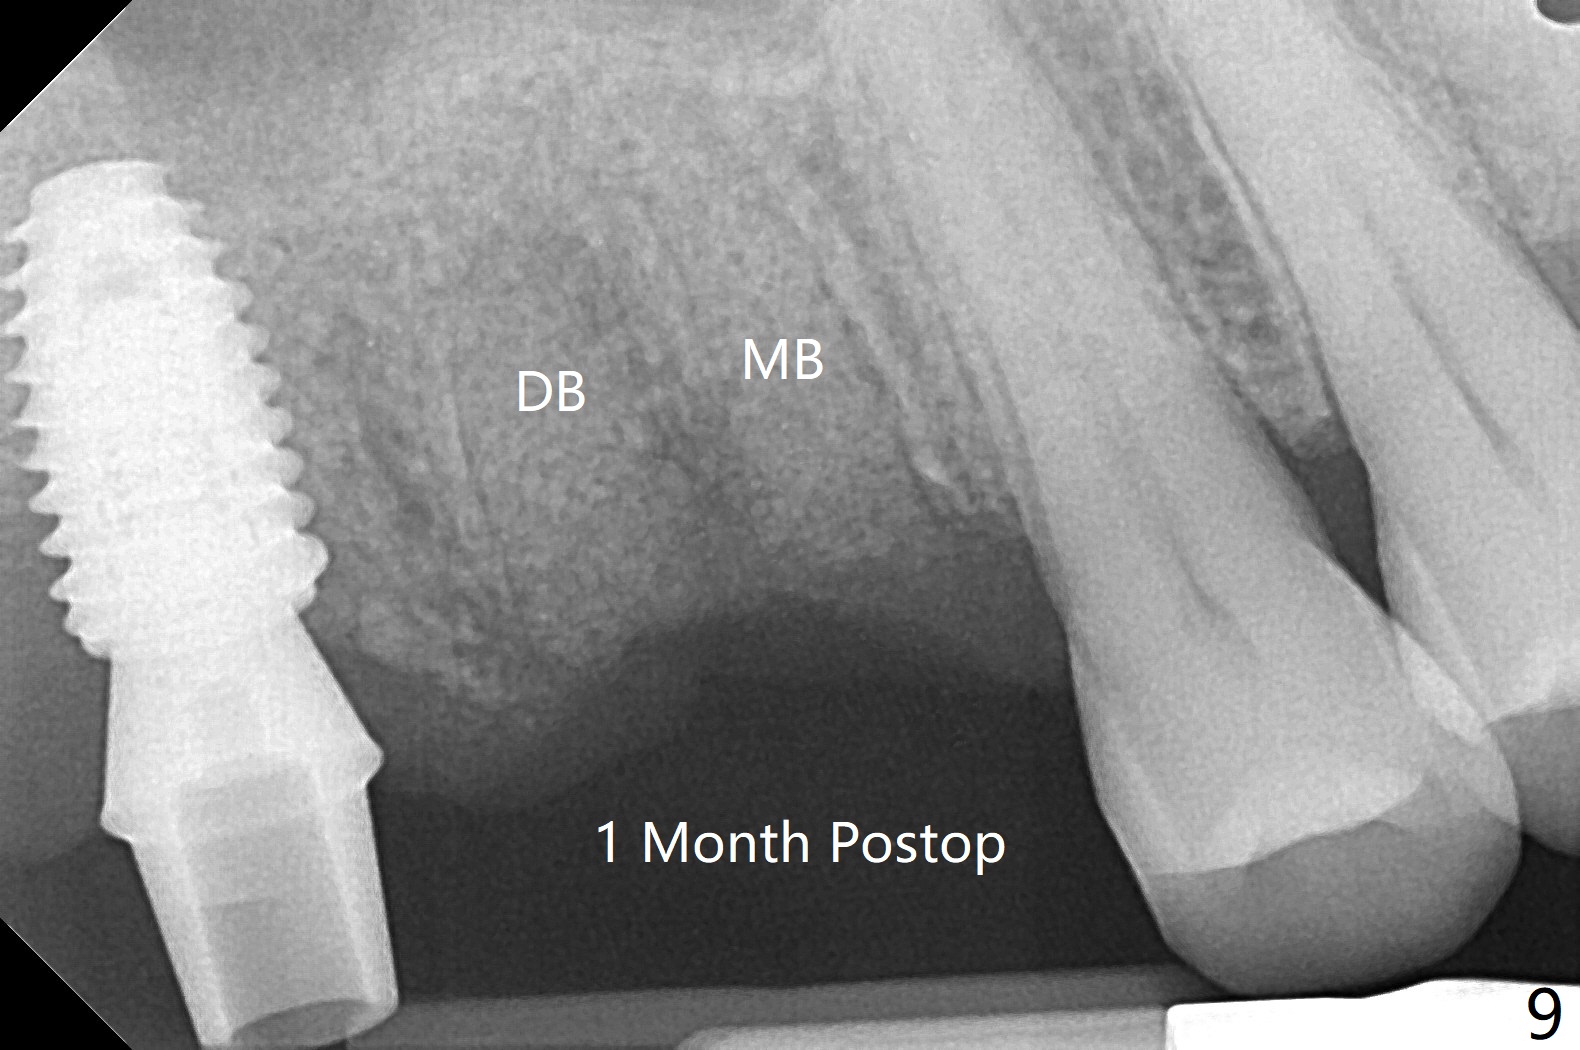

57岁男咬合力大,在右上7植体愈合中,6(3号牙)出现隐裂(图三),根管治疗后完全裂开(图四),需要拔除植骨。由于他特别害怕治疗,包括抽血,开始不想制作粘性骨块,但是考虑到我们最近用的皮质骨粉颗粒细,送到上颌磨牙牙槽窝困难,容易丢失,最后决定抽血提取上清液,制备粘性骨块(图五)。拔牙也有困难,虽然十分松动,但是无法脱位,研究两年前CT,牙根长,弯曲(图一,二),分根后才完成拔除,骨块剪成三块,分别插入三个牙槽窝(图六),覆盖PRF膜和压扁的胶原塞,缝合。术后一个月,角化龈基本保持原位。由于松弛缝合,角化龈有可能增加~6毫米(图七)。而且骨粉好像没有失去(图八,九 (P:腭侧;MB:近中颊侧;DB:远中颊侧))。术后十个月骨质高度降低(图十)。尤其是腭侧,所以植体需要偏向颊侧(图十一:B)。牙冠粘固后8个月,2号牙植体远中骨质吸收(图十二:<)。